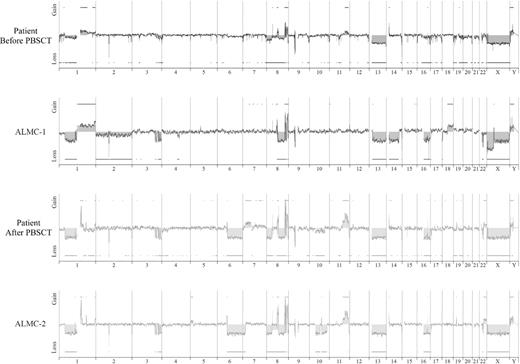

Array CGH analysis

We next used array CGH, a methodology that permits a much higher resolution map of the 4 genomes than that achieved by conventional methods (Figure 4), to test the genetic relationship between the cell lines and the primary patient cells. This analysis permits 2 major conclusions. First, the data clearly demonstrate the overall similarity between the cell lines and the patient primary cells. Second, a number of genetic changes were acquired during the course of disease progression, including regional chromosomal gains in 1q, 11q, and 22q, and losses in 6q, 8p, 10p, and 10q, several of which have been associated with poor prognosis myeloma (reviewed by Tonon30 ). Of interest, 6q deletion is frequently observed in Waldenstrom macroglobulinemia and is associated with features of adverse prognosis.31

Genome-wide high resolution aCGH. Chromosomal copy number alterations across the pre-PBSCT, ALMC-1, post-PBSCT, and ALMC-2 cells are plotted for each probe evenly aligned along the x-axis in chromosomal order.

Figure 4

Although it is beyond the scope of this report to present a detailed analysis of all gains and losses, Figure 5 presents a more detailed view of chromosomes 1, 3, 8, and 22. Chromosome 1q21 is amplified only in the primary patient cells post-PBSCT and the ALMC-2 line. This region has a number of interesting genes that have been shown to play a role in other cancers, including the transcription factor, Arnt32 ; the Bcl2 family member, Mcl133 ; the micro RNA, MIRN55434 ; FLG2, a member of a family of genes whose products interact with intermediate filaments35,36 ; and the DNA-binding histone protein, HIST2H2AB.37  Several regions on chromosome 3 have undergone losses in all 4 samples tested and include ABCC5, a multidrug resistance gene,38  and ATP13A5, a lipid-transporting p-type ATPase.39  The transcription factor, TRMT12 (chromosome 8), has been shown to be amplified in breast carcinoma40  and is amplified in both primary patient samples and both cell lines (Figure 5). Finally, losses were also observed on chromosome 22 in all 4 samples. One of these regions includes the IGL locus and probably reflects genomic DNA lost on chromosome 22 during VJ rearrangement. Consistent with λLC expression, there is a biallelic loss of the κLC locus on chromosome 2p12 in all 4 samples studied (Figure 4). The second region of chromosome 22 loss highlighted involves the NF-2 gene, a known tumor suppressor gene.41,42  Collectively, these data demonstrate how closely the in vitro passaged cell lines resemble the primary patient cells. This analysis also demonstrates how the cell line established from the diagnostic marrow similarly evolved, albeit in vitro, in a way that largely mirrored in vivo evolution of the primary tumor.